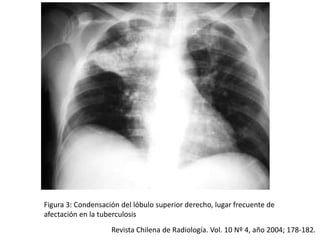

Figura 3: Condensación del lóbulo superior derecho, lugar frecuente de

afectación en la tuberculosis